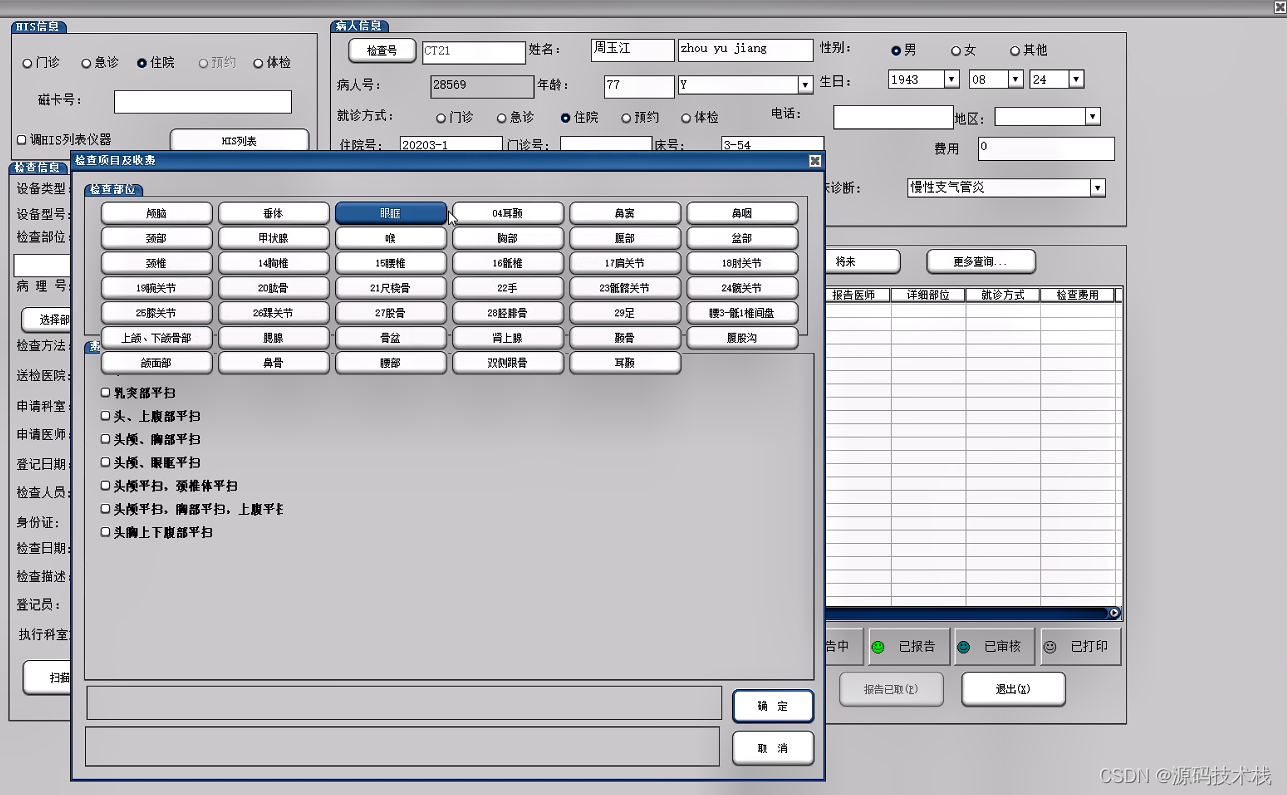

信息预约登记

支持对患者、检查项目、申请医生、申请单据、设备等信息进行管理。且支持检查病人排队管理功能;

支持大屏幕队列显示和语音呼叫;

提供预约调整、插队管理和掉队处理等功能;支持急诊申请优先安排。

PACS流程从病人开始在HIS登记(挂号登记)或在RIS中进行检查登记开始。然后病人进入检查室,技师进行检查,接着阅片、书写报告和影像及图文报告归档。

1. 临床医生在医生工作站中录入电子检查申请单,并将申请单传入RIS系统。

2. 影像检查科室的RIS中对电子检查申请单的信息进行预约、审核、划价确认。